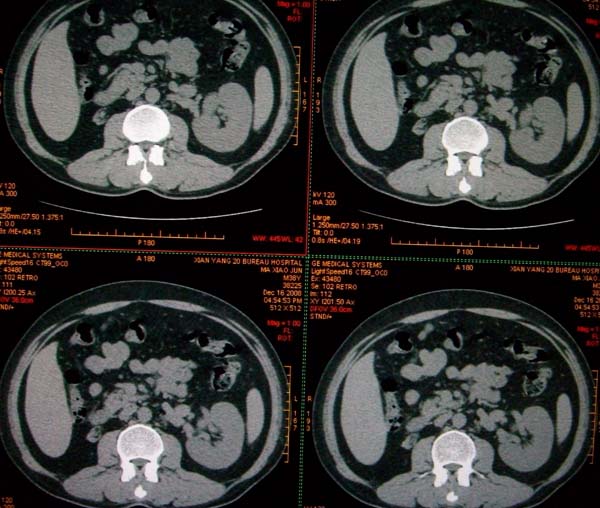

标题: CT17174:M38Y,体检超声提示右肾发育不良,病人无明显不适 [打印本页]

标题: CT17174:M38Y,体检超声提示右肾发育不良,病人无明显不适

右肾发育不良;考虑左肾下极血管平滑肌脂肪瘤可能,建议增强。

右肾微小发育不良  左肾下极错构可能

1)左肾下极占位性病变,不排除肾癌可能;建议行进一步检查。2)右肾发育不良。

左肾下极占位性病变,不排除肾癌可能;建议增强及明确内部组织ct值。右肾发育不良。

右肾发育不良。左肾下极占位。

右肾发育不良。左肾代偿。左肾下极占位,性质待定,建议强化。

右肾发育不良

右肾发育不良。左肾下极占位。建议增强!

右肾发育不良。左肾下极占位。  强化

右肾发育不良。左肾下极囊实性占位,建议增强。